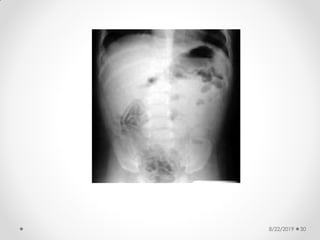

Abdominal X-ray

findings:

• Dilated bowel loops

• Thickened bowel wall

• Fixed dilated loop

• Scarce or absent intestinal gas

• Pneumatosis intestinalis:

• radiologic sign pathognomonic of NEC

• appears as a characteristic train-track

Abdominal X-ray(contd)

• Abdominal free air:

o ominous and usually requires emergency surgical

intervention

• Portal gas

o subtle and transient finding

• Ascites

o late finding

• Left side down (left lateral) decubitus radiography

o allows the detection of intraperitoneal air, which rises

above the liver shadow (right side up) and can be

visualized easier than on other views

8/22/2019 30